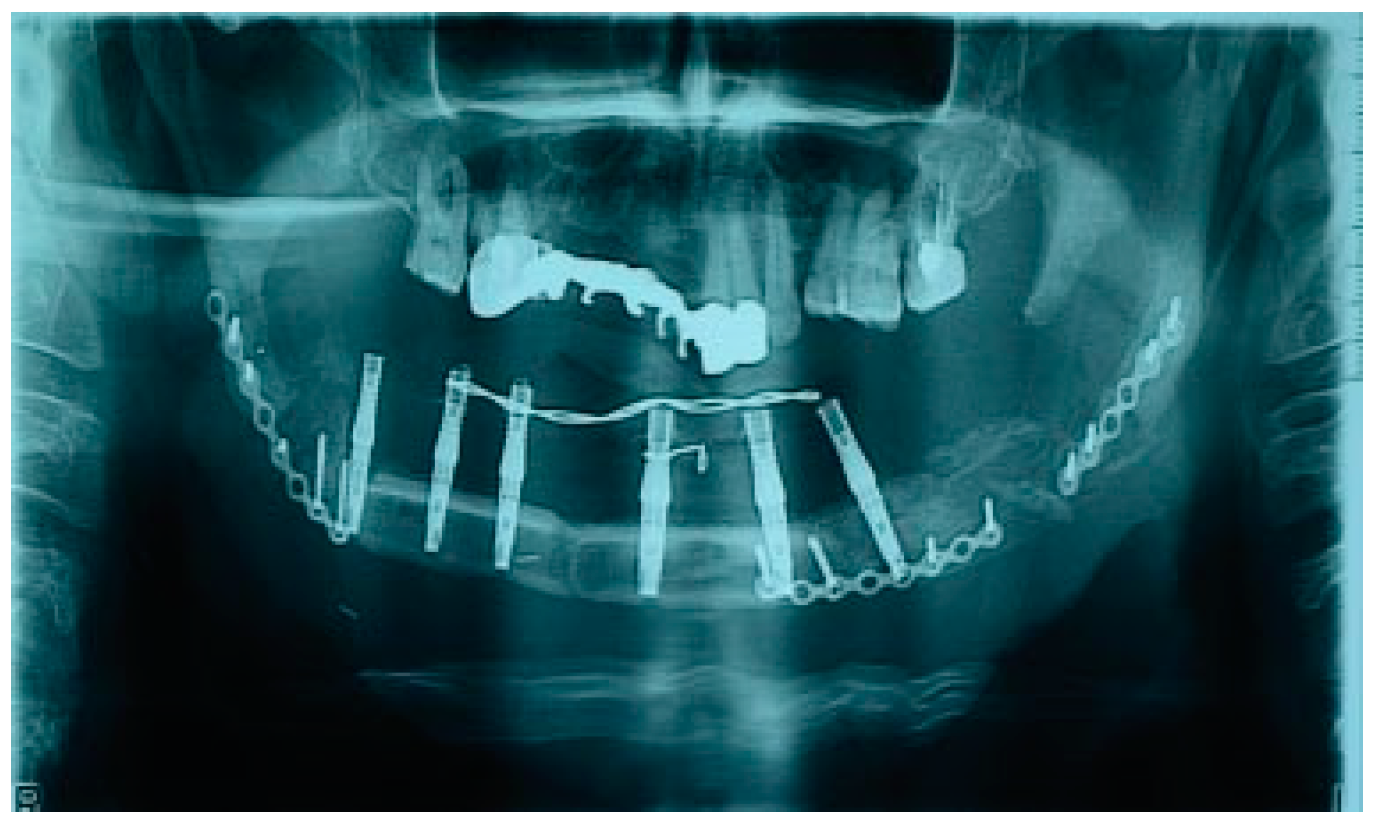

There were no significant complications postoperatively. Postoperative CT and OPG showed bone graft, dental implants, and reconstructive plate to be positioned in accurate anatomical relationship to each other and facial skeleton (Figure 8). A half year later, reconstructive plate was replaced by titanium miniplates (Figure 9).

Figure 8. Postoperative radiology: OPG.